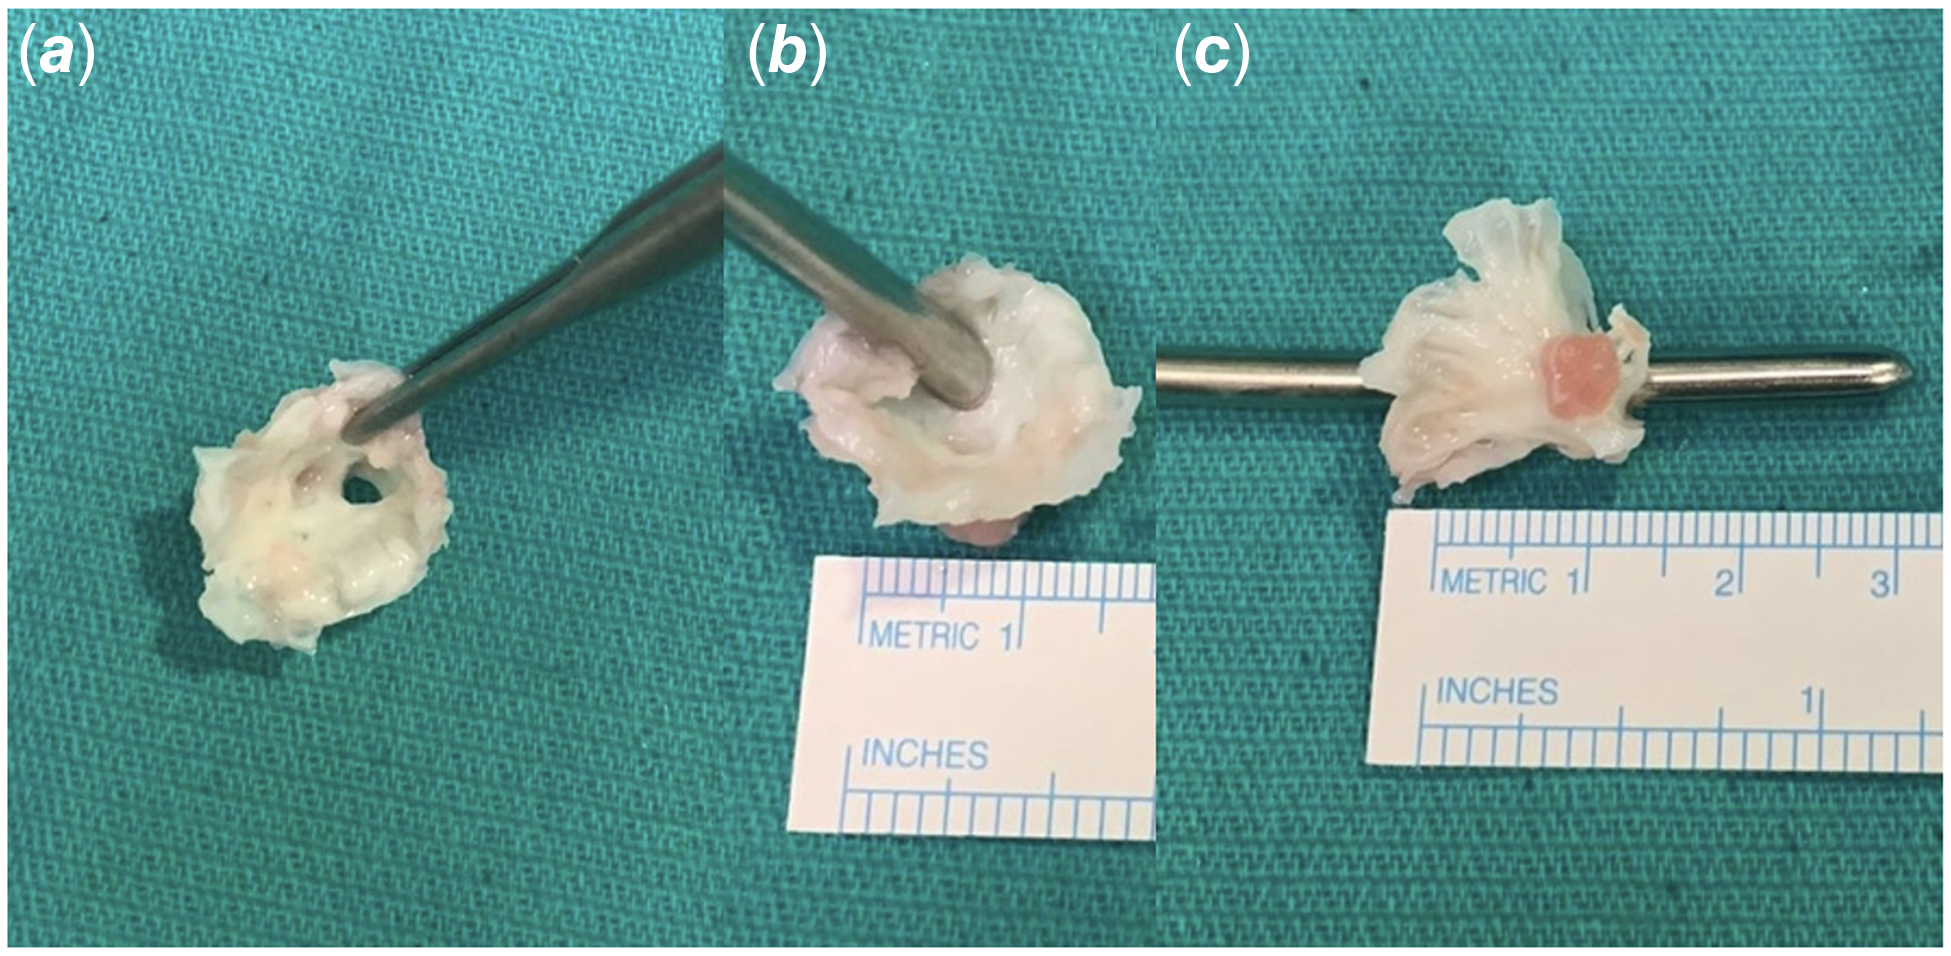

Having cleared the lower respiratory tract infection and upon approval by the infectious diseases team, patient was brought to the operating room. A median sternotomy was done. Left atrium was enlarged and pulmonary veins were dilated. Cardiopulmonary bypass was instituted with standard aortic and bi-caval cannulations. Following the cross-clamp and cardioplegic arrest, left atrium was opened through interatrial groove. Anatomy was inspected. Multilevel complex stenosis of the mitral valve was seen. Annulus and orifice were extremely stenotic. A hypoplastic annulus free of supravalvar involvement was the first finding. Both leaflets were extremely thickened and rolled in addition to being extremely dysplastic. Even a 4 mm dilator was barely able to pass through the extremely narrow valvar opening. Additionally, the papillary muscles were not evenly distributed; one of them was extremely hypoplastic, and they were somewhat close together. The one that predominated was long, angled toward the annulus, bridged by fibrous tissue to the mitral leaflet’s free edge, and situated high in the left ventricle. There were no evident interchordal spaces, and the chordae tendinae were thickened, shortened, and packed into the subvalvar area, which was mostly attached to the dominant papillary muscle (Fig. 2). The extreme morphologic structure made it impossible to perform a decent and long-lasting repair, so the decision was made to replace the valve. Mitral valve and its apparatus were completely excised, leaving adequate rim for replacement sutures. Even after complete excision of the valve, 17 mm Hegar dilator was barely passing through the annulus. Thus, 15 mm mechanical aortic valve was implanted with supra-annular technique in upside-down fashion to prevent heart block, circumflex coronary artery compression, and pulmonary vein stenosis risks. Having implanted the valve, left atriotomy was closed and patient was weaned off cardiopulmonary bypass uneventfully with low dose inotrope. Post-bypass epicardial echocardiography showed good biventricular function, no mitral paravalvular regurgitation, or prosthetic gradient. The aortic cross-clamp and bypass times were 75 and 93 minutes, respectively. Post-operative course was uneventful. The patient was extubated on the day of operation, and drains and wires were removed on postoperative day 3. Pre-discharge echocardiogram showed normal systolic function without any prosthetic valve problem. Subsequently, he was discharged to home on postoperative day 6 with adequate international normalized ratio (INR) follow-up scheme. He is still doing clinically well 25 months after the operation with a mean INR value of 2.6.

Figure 2. Intra-operative resected mitral valve. Severely dysplastic mitral valve ( a ); 4 mm Hegar dilator was barely passing through the valvar orifice ( b ); Severely dysplastic mitral valve with subvalvar apparatus showing one dominant and one another hypoplastic papillary muscles ( c ).

In our patient when the mitral valve was examined intraoperatively, it was found to be not appropriate for satisfactory repair as the valve was showing severe stenotic features in multilevel fashion. First, the annulus was hypoplastic with no supravalvar involvement. Secondly, both leaflets were severely dysplastic, thickened, and rolled. Valvar orifice was so small even 4 mm dilator was barely passing through. Third, there were two asymmetric papillary muscles, one being severely hypoplastic, and they were closely spaced. The dominant one was elongated, displaced toward the annulus, connected to the free edge of the mitral leaflet by a bridge of fibrous tissue, and highly positioned within the left ventricle. It had a wide base and was attached to the lateral side of the left ventricle. Subvalvar area was crowded with chordae tendinae were shortened and thickened with the absence of interchordal spaces and predominantly connected to the dominant papillary muscle.